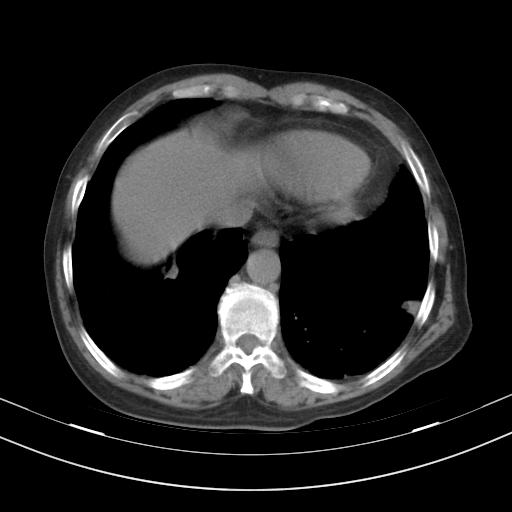

老年女性,嗜睡3天,意识模糊。轻咳,无发热。

1)两肺感染性病变;建议抗炎治疗后复查。2)纵隔淋巴结肿大。3)左侧胸腔积液。

3)左侧胸腔积液。